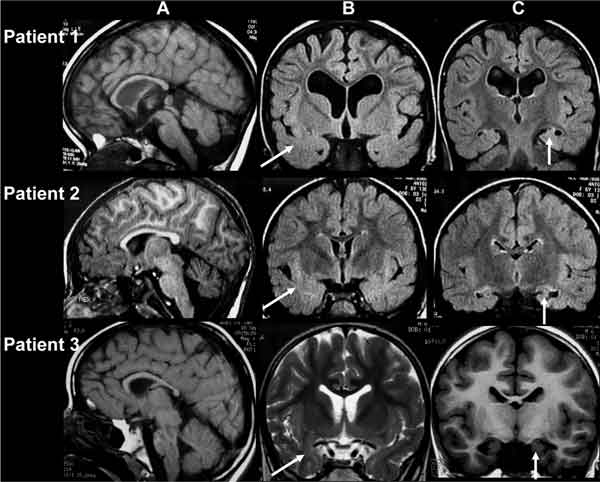

L’Encefalopatia traumatica cronica (CTE) e’ stata fino ad oggi diagnosticata soltanto attraverso l’autopsia. La malattia, che colpisce molti giocatori di football, baseball e di boxe dal momento che deriva da forti traumi cranici, e’ sotto esame per individuare metodi che consentano di individuarle quando un soggetto e’ ancora vivo. Tra questi, quello ideato dalla University of California, Los Angeles, un biomarcatore in grado di attaccarsi a grovigli di proteine tau cosi’ da mostrarsi su scansioni PET di persone vive. Gary Small della UCLA e’ attualmente al lavoro per uno studio pilota su giocatori di National Football League in pensione, che vengono sottoposti a scansioni cerebrali.

Se l’esperimento ha successo, il suo lavoro andrebbe a ri-orientare la branca delle lesioni alla testa per salvare vite umane, piuttosto che limitarsi ad accertarle dopo la morte. Il mese scorso il giocatore Junior Seau si e’ tolto la vita nell’appartamento di Oceanside, California: il suo cervello e’ stato richiesto sia dal Brain Injury Research Institute della UCLA sia dal Boston University’s Center for the Study of Traumatic Encephalopathy, le due banche cerebrali piu’ importanti per lo studio di danni in ex giocatori. Se otterranno il consenso della famiglia, il cervello di Seau sara’ analizzato per verificare se, come ci si aspetta, i tessuti mostrano un accumulo di proteina tau in grovigli simili a quelli presenti nei malati di Alzheimer. “La scansione delle tau e’ come il S anto Graal del danno cerebrale cronico”, ha detto Julian Bailes, uno dei fondatori del Brain Injury Research Institute. Il marcatore sotto esame alla UCLA e’ il piu’ promettente tra i vari progetti di ricerca sulla CTE.